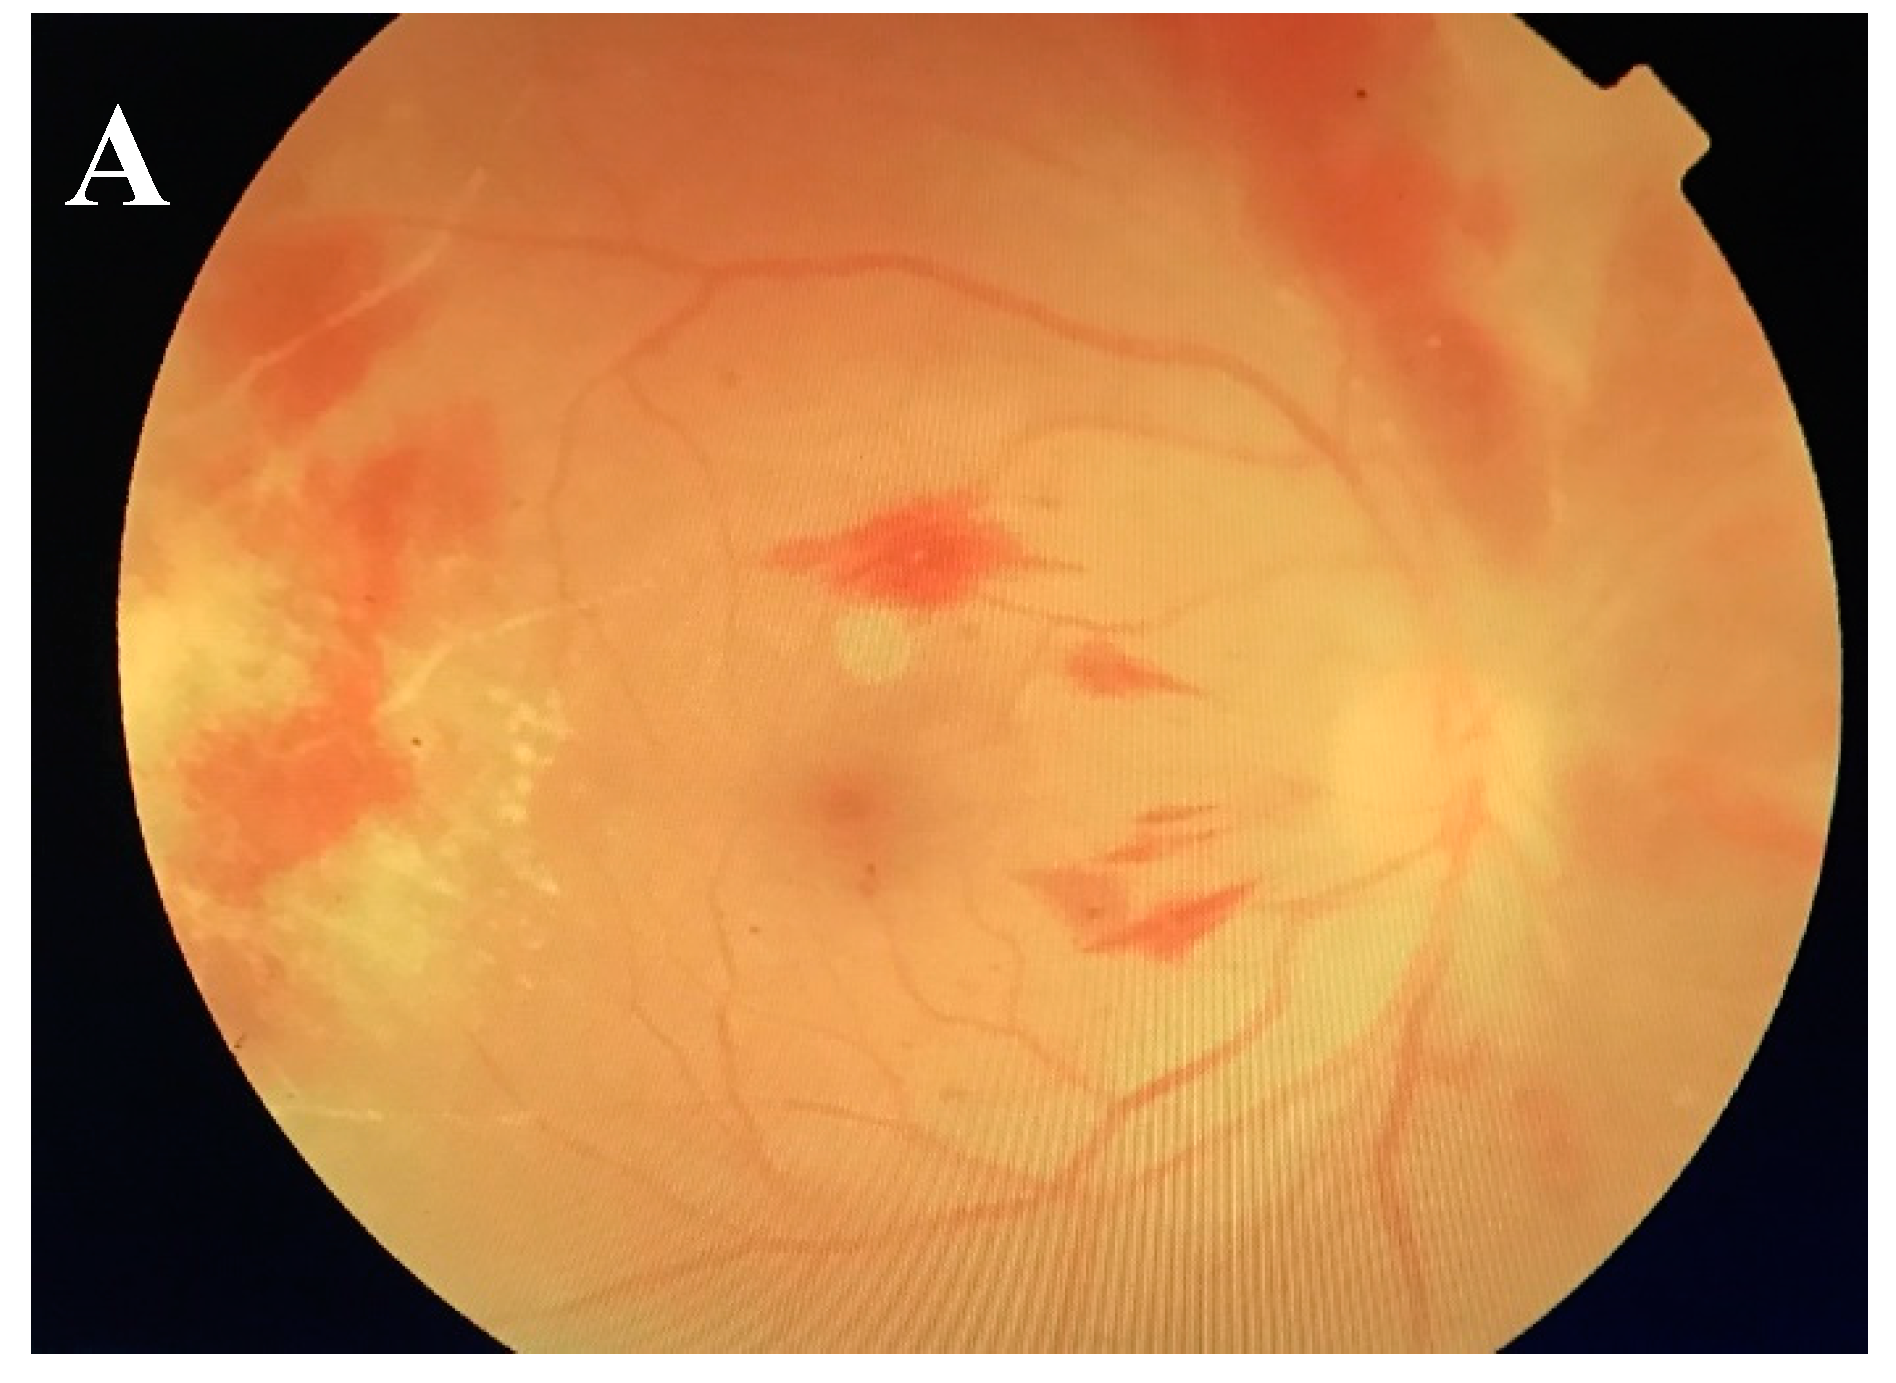

2.2. Ocular Viral Infections and the Challenges of Conventional Antiviral Treatment